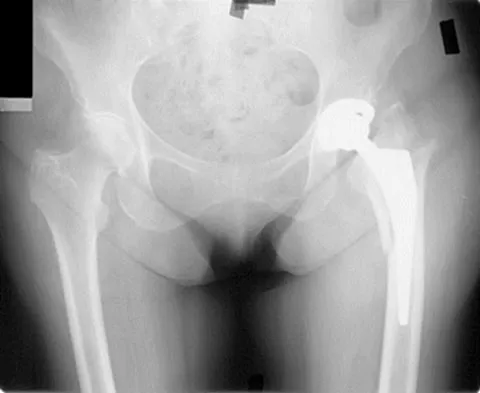

A 53-year-old patient is seen in the emergency department after sustaining a fall onto her left hip. A current radiograph is shown in Figure 40. What is the best treatment option?

The patient has sustained a Vancouver B2 periprosthetic femoral fracture (a femoral fracture that occurs around or just distal to a loose stem, with adequate proximal bone stock). The stem is no longer fixed to proximal bone; therefore, retention of the femoral component is not recommended. Nonsurgical management is contraindicated because of the high risk of nonunion and malunion with significant component settling in the distal fragment and leg shortening. Revision femoral arthoplasty must attain distal fixation in adequate host bone, which is usually successful with a porous-coated cylindrical stem. Parvizi J, Rapuri VR, Purtill JJ, et al: Treatment protocol for proximal femoral periprosthetic fractures. J Bone Joint Surg Am 2004;86:8-16.